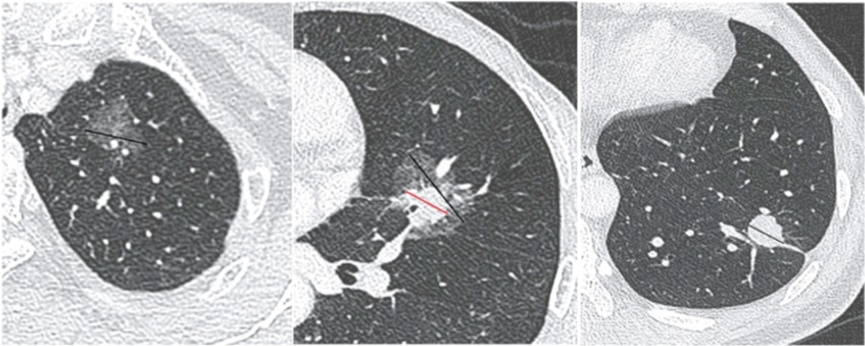

按照密度区分,有实性结节、部分实性结节(混合性结节)和磨玻璃结节。实性结节在影像上显示为密度均匀的白色阴影;磨玻璃结节如同磨砂玻璃,呈半透明状;部分实性结节则兼具两者特点。其中,部分实性结节恶性的可能性相对较高。

磨玻璃结节、混杂型磨玻璃结节、实性结节